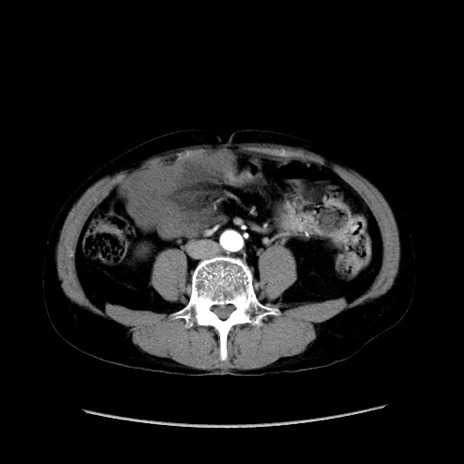

症例37(横断像)

【症例】40歳代 男性

【主訴】腹痛

【現病歴】4時間ほど前に電車に乗車中に臍部上より腹痛出現。徐々に増悪し起立困難となり、救急外来受診。生ものは数日食べていない。今朝お雑煮を食べた。

【身体所見】BT 36.8℃、BP 117/84mmHg、HR 91/min、SpO2 97%、苦悶様、腹部:臍上部広範囲圧痛あり、反跳痛±

【データ】WBC 8100、CRP 0.03